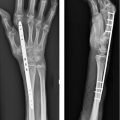

After appropriate alignment has been obtained and a central K-wire has been placed for a cannulated screw, it may be useful to place a second K-wire, eccentrically across the fracture site as an antirotation pin prior to screw insertion. Alternatively, if the first pass of a K-wire ends eccentrically, this should be left in place as an additional visual cue to place a second K-wire centrally and the first will take on the function of an antirotation pin (► Fig. 41.4).